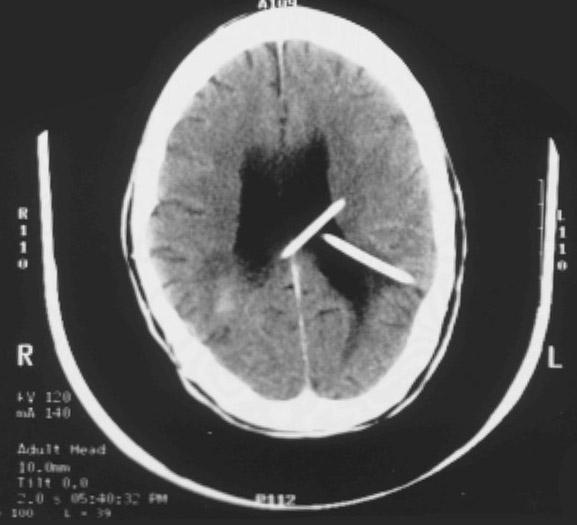

This is a computed tomographic (CT) scan demonstrating enlarged lateral ventricles in a patient with hydrocephalus. This condition has been treated by placing two shunts (the thin white objects).